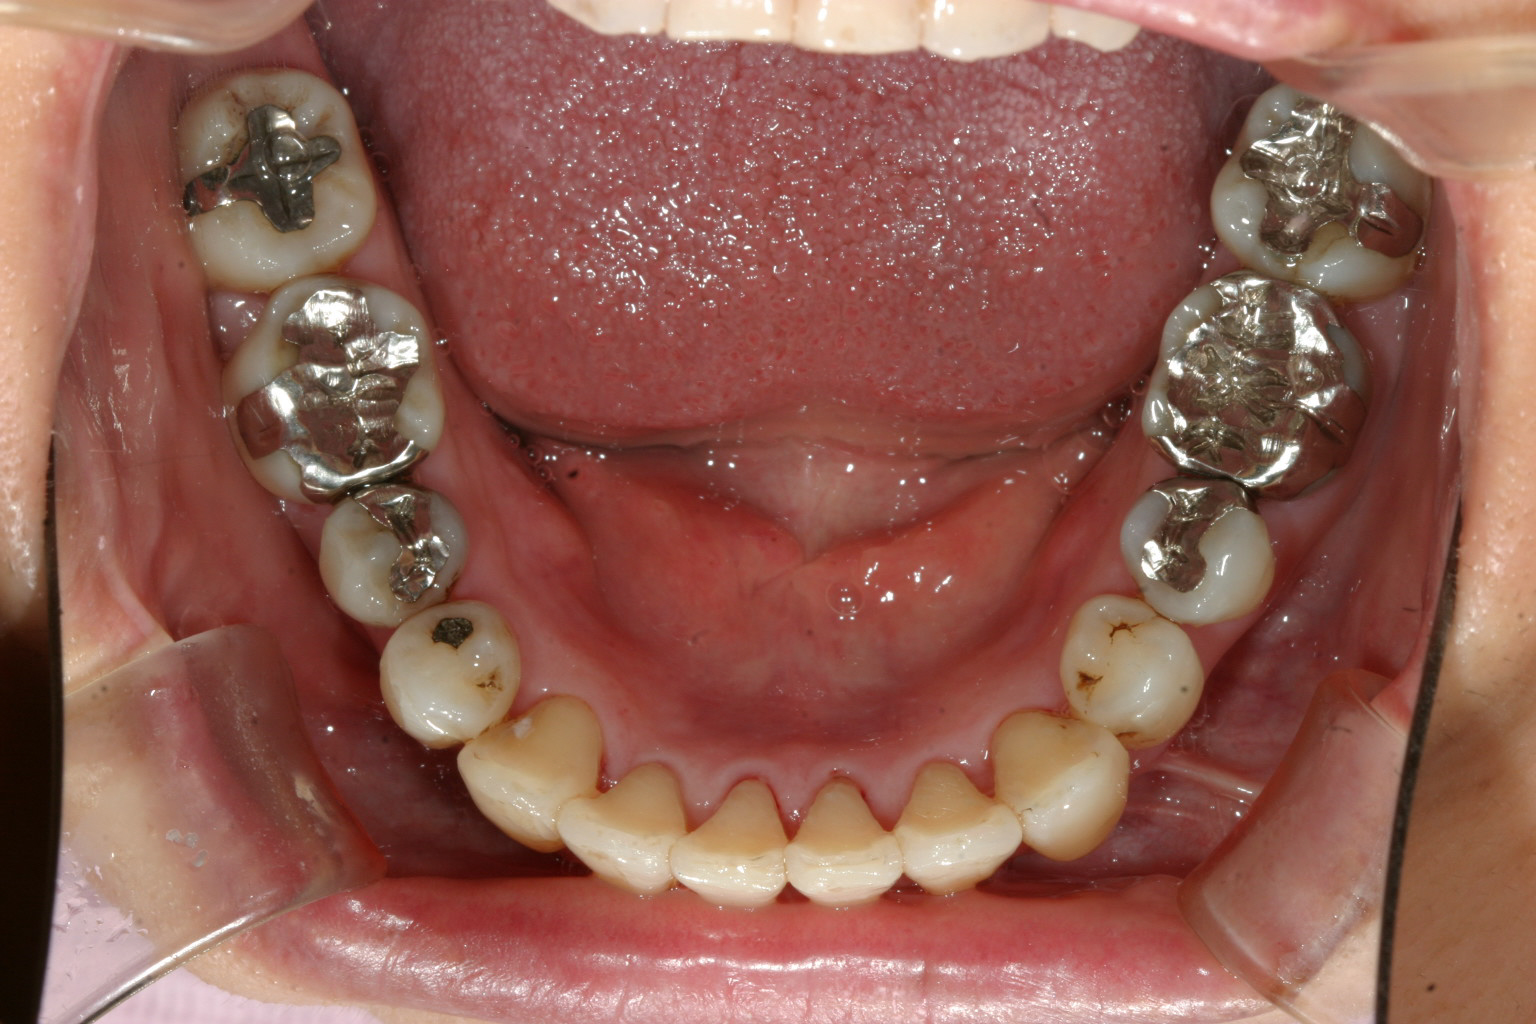

下顎も歯があちこち回転してますでしょ~ これはかなり大変です。